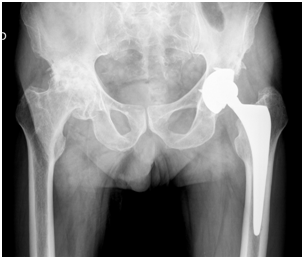

It is a male patient, who is currently 83 years old, followed in outpatient orthopedics since 2002 because of bilateral coxarthrosis. In 2003 he underwent left total hip arthroplasty uncomplicated, with good functional outcome and regression of symptoms (Figure 1).

Figure 1 Pre-operative X-Ray.

In 2004 while preparing for right THA, it was identified thrombosed aneurysm of the right popliteal artery in need of carrying out femoral-popliteal bypass. Because of this major vascular event, the right hip arthroplasty has been successively delayed until 2012. At this time, and after balancing the risks and benefits, was decided to perform a right cemented THA. The surgery and the postoperative elapsed normally without any adverse vascular, orthopedic or neurologic events (Figure 2).

Figure 2 Post-operative X-Ray.